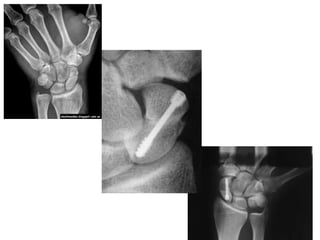

TRATAMIENTO QUIRÚRGICO

• Indicación: fracturas con desplazamiento,

angulación o mala alineación del carpo

Agujas de Kirschner

- Percutáneas

- No requiere

estiloidectomía o abordaje

ampliado

- Menos estable

Compresión con tornillos

Tornillo de Herbert

• Reducen período de

inmovilización

• Fijación interna sólida

• Efecto arrastre entre

los dos fragmentos

• Compresión en foco

de fractura

• No requiere nueva

cirugía